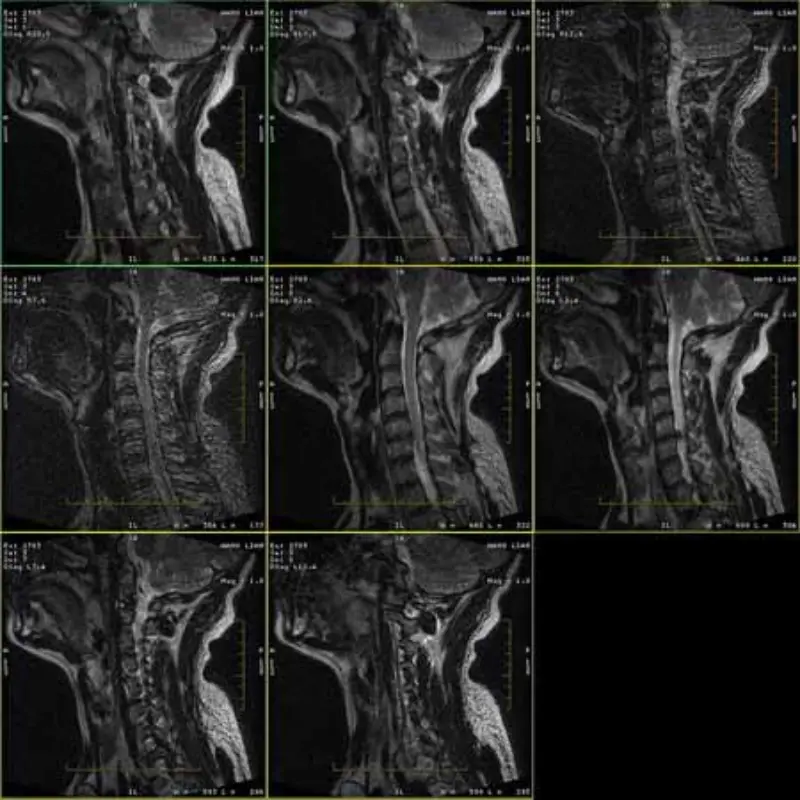

Gambar protokol FRFSE dan GRE memiliki bayangan dan terkadang gambar SNR rendah muncul dalam satu rangkaian. Tapi gambar protokol SE normal.

Silakan lihat lampirkan gambar.